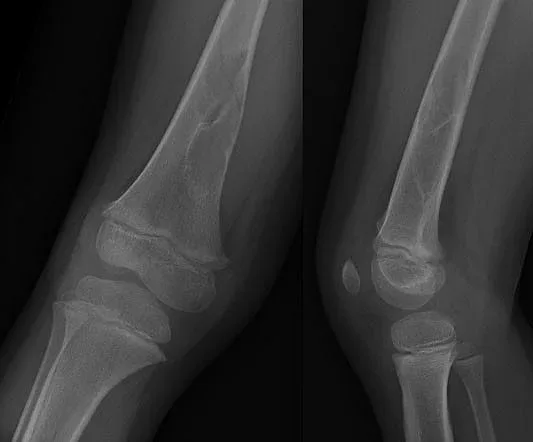

Детето постъпва в лечебното заведение с тежката диагноза Сарком на Юинг, обхващащ цялото ляво бедро. След проведена химиотерапия лекарите пристъпват към премахване на тумора - с цялата бедрена кост и заместването ѝ с мегапротеза.

"Тази протеза е такава, че ако оперираният крайник изостане в растежа си, в сравнение със здравия крак, след приключване на костния растеж на пациентката, ние имаме възможност в определен етап да уеднаквим крайниците, като подменим някой от модулите, които се разполагат в самия имплант", обясни д-р Кирчо Патриков, гл. асистент в болницата по ортопедия.

Операцията продължава над 4 ч. и е първата такава, извършена от изцяло български екип. Две седмици по-късно 13-годишното дете вече прави първите си стъпки.